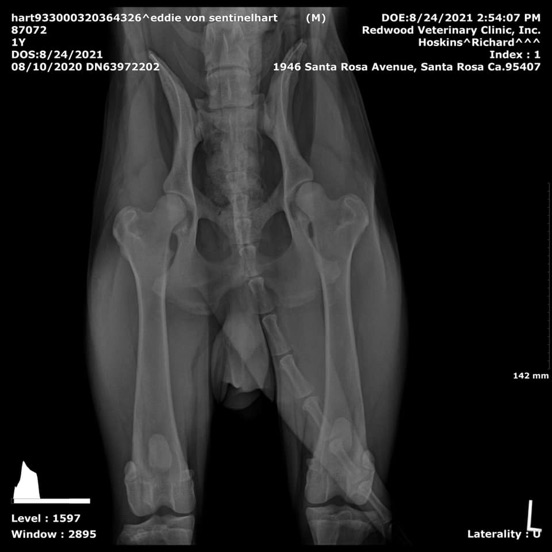

SV Hips A1

SV Elbows  Normal